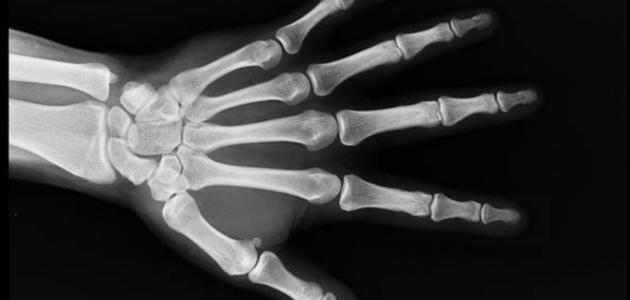

علامات سرطان العظام

علامات سرطان العظام ‘); } سرطان العظام هو أحد السرطانات غير الشائعة بكثرة، التي تبدأ بأي جزء من عظام الجسم، غير أنها تؤثر في الأغلب في العظام الطويلة المكونة للذراعين والساقين، وهناك أنواع عديدة لسرطان العظام يصيب معظمها الأطفال بشكل…